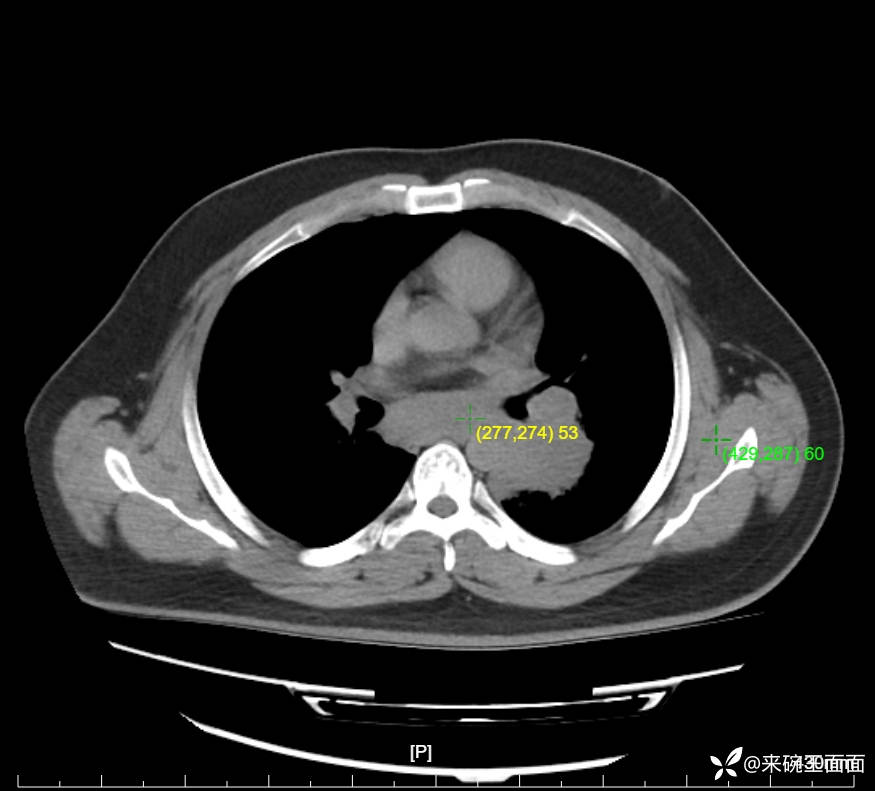

性别:男

年龄:27岁

主诉:胸闷胸痛数月余,休息后可自行缓解,无咯血症状。

个人史:数年吸烟史,具体不详。